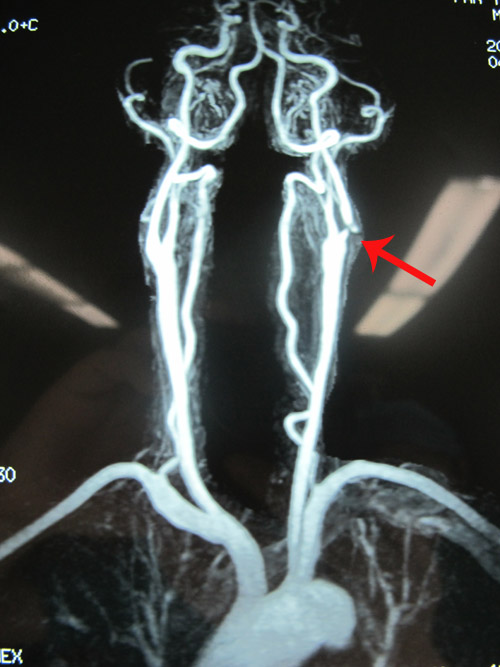

颈部血管超声:双侧颈动脉粥样硬化斑块形成;左侧颈内动脉重度狭窄;左侧股总动脉粥样硬化小斑块形成

冠状动脉+左心室+颈动脉造影示:X综合征;左颈内动脉狭窄

MR示:左侧颈内动脉起始分叉处节段性狭窄

该患者中年男性,偶有头晕不适,完善血管超声,MRA及颈动脉造影检查见颈内动脉近端90%节段性狭窄,心肺功能大致正常,有指征行左侧颈内动脉内膜剥脱术。